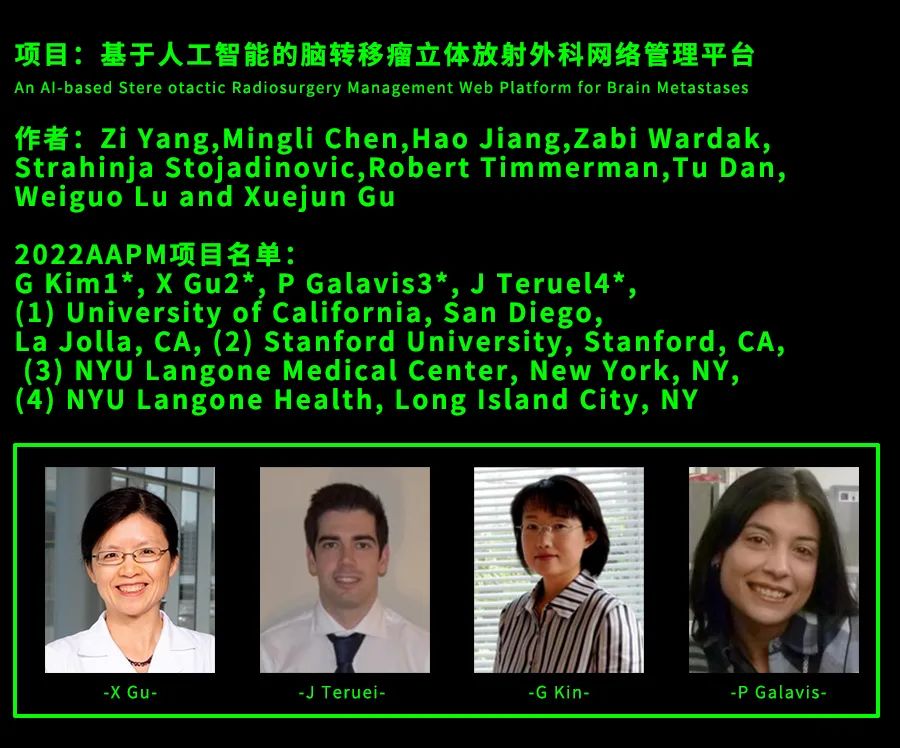

所以他找到了美国西南医学中心、斯坦福大学,寻求合作。

在众人的帮助和努力下,历经多年,终于在不久前开发出了以下三种 AI 模型:

自动勾画 / 标记脑转移瘤病灶的模型;

基于 SVM-放射组学,能快速减少假阳性的模型;

基于优化辐射剂量图,能快速分割多个病灶到不同治疗疗程的模型。

三种模型相辅相成,对应到医生的工作流程中,能大幅减少使用立体定向放疗时的工作量。

这个项目,目前已经在 2022 年 AAPM 春季临床会议上发表,再一次取得了业内的广泛认可。

coolwulf 与合作学者们,也正在加快步伐,试图让整个立体定向放疗社区都能投入使用。

而在采访中,coolwulf 多次提到,能有今天这个成果,绝不是他一个人的功劳。

他希望,差评君能把合作者的名单都公布出来,因为这里的每个人,都是默默和癌症战斗的英雄。